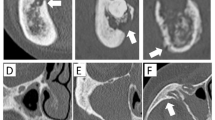

To categorize the imaging findings, the following features were evaluated by H.S., who has 20 years of experience as an oral and maxillofacial radiologist: (1) bone resorption, (2) osteosclerosis, (3) clarity of the mandibular canal, (4) periosteal reaction, (5) cortical bone perforation, (6) sequestrum (necrotic bone), and (7) pathological fracture. The results of the CT images were considered the gold standard for determining the presence or absence of each imaging finding. The detailed criteria for each diagnostic trait were as follows: (1) Bone resorption (Fig. 1): decreased CT values in the mandibular molar region compared with those in the contralateral region, an unaffected site on CT images, increased radiolucency in the same area on panoramic radiographs and clear bone resorption (bone defect) areas in T1- and T2-weighted fat-suppressed MR images. (2) Osteosclerosis (Fig. 2): Increased CT values in the mandibular molar region compared with the contralateral unaffected site on CT images, increased radiopacity in the same area on panoramic X-ray images, and clear areas of bone sclerosis in T1- and T2-weighted fat-suppressed MR images. (3) Clarity of the mandibular canal (Fig. 3): Clear visibility of the mandibular canal on CT images or panoramic radiographs compared with the unaffected contralateral site and clear visibility of the mandibular canal on T1- and T2-weighted fat-suppressed MR images. (4) Periosteal reaction (Fig. 4): Increased CT values outside the buccal, lingual or inferior cortex on CT images; increased radiopacity outside the inferior mandibular cortex on panoramic radiographs; and continuous areas of bone signal intensity outside the buccal, lingual or inferior cortex on T1- and T2-weighted fat-suppressed MR images. (5) Cortical bone perforation (Fig. 5): Discontinuity of the buccal, lingual or inferior cortex on CT images; discontinuity of the inferior mandibular cortex on panoramic radiographs; and discontinuity of the buccal, lingual or inferior cortex on T1- and T2-weighted fat-suppressed MR images. (6) Sequestrum (necrotic bone) (Fig. 6): Presence of bone islands with high CT values within the low-CT-value regions in the mandibular molar region on CT images, radiopacity within the radiolucency area in the mandibular molar region on panoramic radiographs, and no signal areas in the mandibular molar region on T1- and T2-weighted fat-suppressed MR images. (7) Pathological fracture (Fig. 7): presence of fracture lines and/or displacement of bone fragments on CT, panoramic, or T1- and T2-weighted fat-suppressed MR images.

Case with a sequestrum. An 81-year-old male underwent extraction of the left lower second premolar at a dental clinic. Nonhealing extraction socket complications persisted, with periods of improvement and worsening. CBCT imaging revealed sequestrum in the left mandibular molar region, leading to referral to our hospital. He was diagnosed with bacterial OM because of exclusion from the ORN or MRONJ criteria. (A) CT image (bone mode) showing islands of high CT values within the low CT value area (arrow). (B) Panoramic X-ray image revealing radiopaque areas within the radiolucent area (ellipse). (C, D) T1-weighted MR image and T2-weighted fat-suppressed MR image demonstrating no signal intensity region suspected to be sequestrum (arrows).